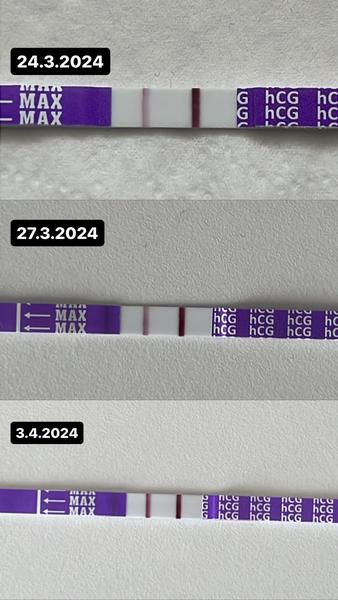

@zanzilady 1. odber - 19.3. - 9,14 potom 2. odber - 26.3. - 104,9 a dnes 3. odber 3.4. - 409. Medzi 1. a 2. odberom je nárast ok. Ale madzi 2. a 3. je nižší ako by mal byť..

Žienky tak nakoniec odpísali ešte dnes. HCG mám 409. Mám sa zastaviť v piatok na sono tak ako sme boli dohodnuté.. Dúfala som teda vo vyšší nárast 😢

@katariiinkaa a testy su krásne 😍😍😍. Ja verím že je to malý bojovník a dosiahnete to úspešne až do konca 🙏🍀❤️

@katariiinkaa na to sa tak krásne pozerá. Držím palčeky a snáď sa aj my ostatné čoskoro dočkáme 🥰

@katariiinkaa testy su krasne…. Drzim palce aby uz bolo na sone nieco vidno 😉